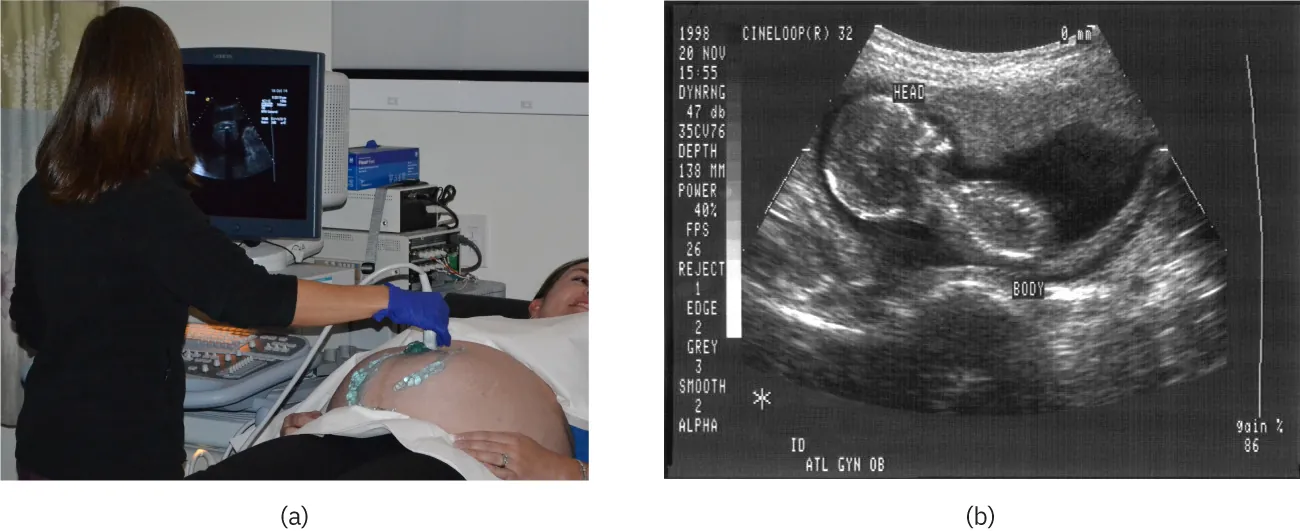

An ultrasound image of a 21 week old fetus.

Figure 17.40 Ultrasound is used in medicine to painlessly and noninvasively monitor patient health and diagnose a wide range of disorders. (credit: abbybatchelder, Flickr)

Any sound with a frequency above 20,000 Hz (or 20 kHz)—that is, above the highest audible frequency—is defined to be ultrasound. In practice, it is possible to create ultrasound frequencies up to more than a gigahertz. (Higher frequencies are difficult to create; furthermore, they propagate poorly because they are very strongly absorbed.) Ultrasound has a tremendous number of applications, which range from burglar alarms to use in cleaning delicate objects to the guidance systems of bats. We begin our discussion of ultrasound with some of its applications in medicine, in which it is used extensively both for diagnosis and for therapy.